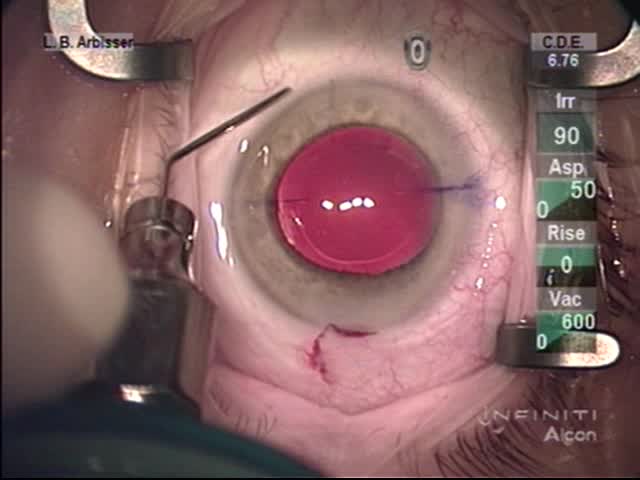

Posterior Optic Capture Demonstration

Lisa Brothers Arbisser, MD